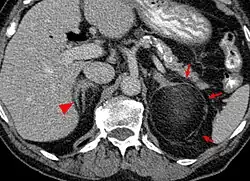

Myelolipome sind gelbe bis bräunliche, wenige Millimeter bis 30 cm große, umschriebene, jedoch nicht gekapselte Tumoren. Sie treten üblicherweise solitär und einseitig im Bereich einer Nebenniere auf, werden selten jedoch auch bilateral und/oder außerhalb der Nebenniere (z. B. im Retroperitoneum, Mediastinum, der Leber, in Muskelfaszien) gefunden. Mikroskopisch setzt sich der Tumor aus reifem Fettgewebe und myeloiden Zellen zusammen. Gelegentlich werden Infarktareale, Einblutungen oder knöcherne Metaplasien beobachtet.[1][2]

Die Mehrzahl der Myelolipome sind asymptomatisch und werden zufällig, etwa im Rahmen radiologischer Untersuchungen oder einer Obduktion gefunden. Nur gelegentlich, insbesondere bei größeren Tumoren, berichten betroffene Patienten von Bauch- oder Flankenschmerz. Selten bestehen endokrine Störungen wie das Cushing-, Conn-Syndrom oder eine angeborene Nebennierenhyperplasie.[1]